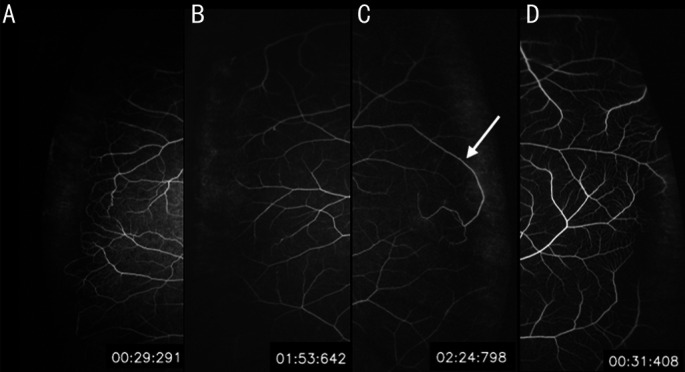

For qualified UWF images, PAFT and VFT was recorded (Figure 1). PAFT was calculated from the beginning of arterial filling to the completion of arterial trunk filling in temporal peripheral region. VFT was calculated from the beginning of laminar flow of the first vein to the complete filling of all veins. Cilioretinal artery and its drainage vein were distinguished and excluded from the calculation.

Figure 1. Representative images for evaluation on the PAFT and VFT in UWF FA.

A: PAFT was calculated from the beginning of arterial filling; B: VFT was calculated from the beginning of laminar flow, starting form areas around the papilla; C: The photo previous to the arterial filling end point, arterial forward continues moving; D: The arterial filling end point, arterial forward reached the temporal peripheral retina, and is previous to the next photo in E; E: The peripheral capillary network (arrow) was shown; F: Venous filling end point, laminar flow in the main trunk was disappeared.

In UWF-angiography, arterial forward took several seconds to reach the temporal peripheral retina. The arterial filling end point was decided by the photo previous to the one that the peripheral capillary network was shown (Figure 1D). During the arterial filling process, the vein from the perfused area started to show laminar flow, starting form areas around the papilla. As the filling process continued, each small vein gathered and filled the main trunk vein completely. When the laminar flow in the main trunk was disappeared, the venous filling process was considered over.